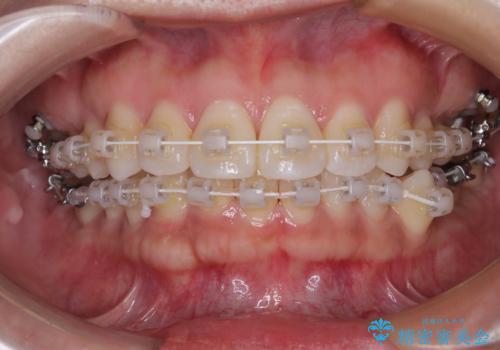

矯正中の見た目にも配慮し、プラスチックブラケット+コーティングワイヤーの目立ちにくい審美装置を採用しました。

そこで本症例では、上顎右側にアンカースクリュー(矯正用インプラント)を埋入し、そこからゴムかけ(顎間ゴム)を行うことで、下顎の正中を右方向へコントロール。

これにより、左下小臼歯がく並ぶためのスペースを確保することができました。